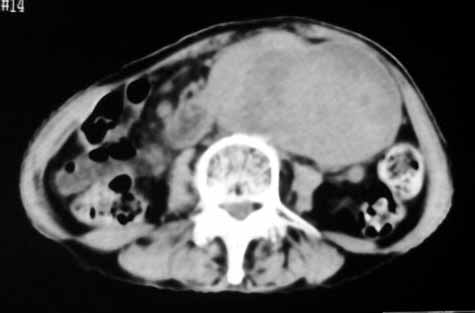

1.中腹部腹主动脉旁可见巨大包块影,其形态似为2个(或分叶),与腹主动脉分界不清,边界较清,其内密度不均匀(稍高、不匀称低密度),腹膜后未见确切肿大淋巴结...性质?考虑腹主动脉瘤可能性大,不排除平滑肌瘤及畸胎瘤可能,建议增强ct;

考虑:1、左侧腹膜后占位性病变(以间叶源性肿瘤可能性大);

腹膜后软组织肿块,密度不均匀,病灶分叶,降主动脉受浸犯

考虑:来源于腹膜后间叶组织的肿瘤

脂肪肉瘤,平滑肌肉瘤的可能性大。支持!(本例关键是定位,仔细分析,可以观察到主动脉被包埋于肿瘤内,因此可定位于—来源于腹膜后的实性肿瘤。)

腹膜后肿块侵犯腹主动脉及肠系膜上动脉,肿块密度不均,1来源间叶组织肿瘤,2肠系膜恶性肿瘤可能大,